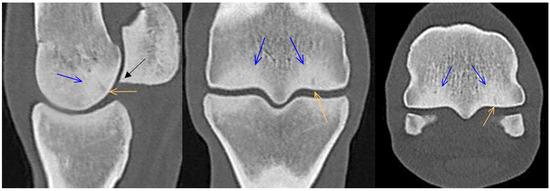

3.1. Third Metacarpal Bone